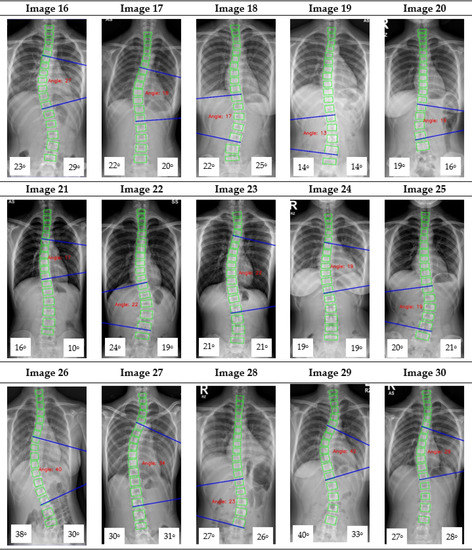

The Cobb angle measurement of the scoliotic spine is prone to inter- and intra-observer variations in the clinical setting. This paper proposes a deep learning architecture for detecting spine vertebrae from X-ray images to evaluate the Cobb angle automatically. The public AASCE MICCAI 2019 anterior-posterior X-ray image dataset and local images were used to train and test the proposed convolutional neural network architecture. Sixty-eight landmark features of the spine were detected from the input image to obtain seventeen vertebrae on the spine. The vertebrae locations obtained were processed to automatically measure the Cobb angle. The proposed method can measure the Cobb angle with accuracies up to 93.6% and has excellent reliability compared to clinicians’ measurement (intraclass correlation coefficient > 0.95). The proposed deep learning architecture may be used as a tool to augment Cobb angle measurement in X-ray images of patients with adolescent idiopathic scoliosis in a real-world clinical setting. Full article

Show Figures

Figure 1